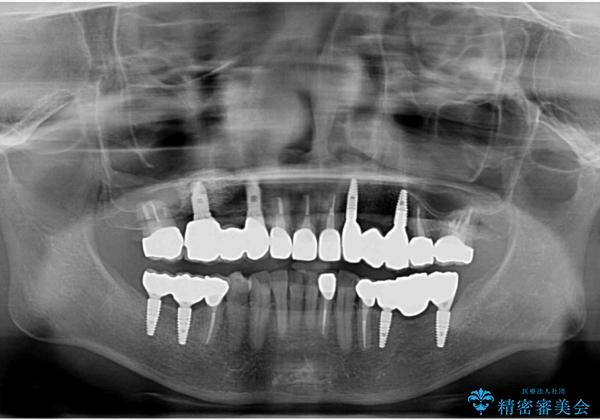

全顎的 虫歯治療 インプラント補綴

今後延々と治療を繰り返さないために、全ての銀歯を外し虫歯を丁寧に取り切り、根管治療を行い、残せない歯は抜去を行った上でインプラント治療を行っていくことで全体的な治療を計画していくこととなりました。

工程数が多かったため治療期間はかかりましたが、しっかりと安定した噛み合わせ、審美的な口腔内環境を達成することができ大変満足していただくことができました。